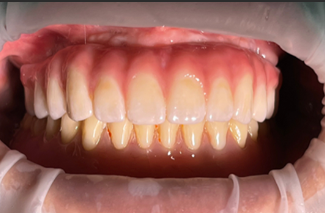

2018년 풀아치 환자분 (당시 40대 남자)

현재도 잘 사용중이세요

잇몸 반응도 지르코니아라 깨끗하구요

곱창집에서 곱창도 드시더라구요..

(곱창집 갔다가 우연히 마주침)

연구에서도 13년 성공률이 93프로에 달해요..